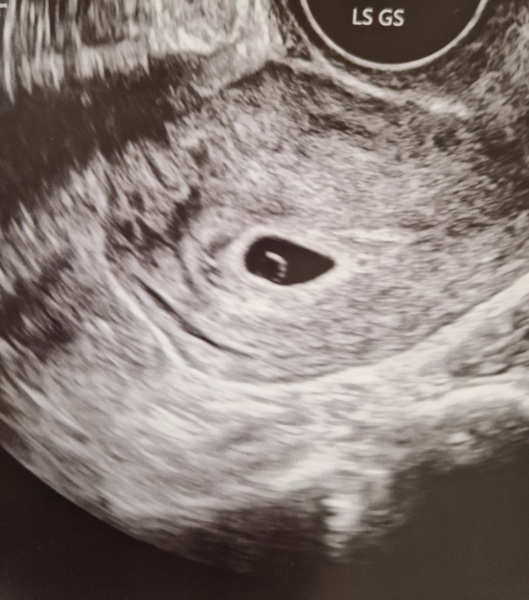

I had my scan at the EPU. Everything looked perfect and the sonographer knew I was about 5w2d without me telling her. Too early to see much but all looked on track, could see the yolk sac and gestation sack and a tiny dot. They thought the spotting last weekend was probably implantation but still suggested I should take progesterone due to previous loss. Has anyone taken it and not had side effects? I'm happy it was a positive outcome. Will get rescanned when back from my trip in 4 weeks. Will be hard to wait but hope all will go well.

@WolfMother326 ahhh first scan pic of the thread 🥹 amazing and I'm so pleased it all looks well. Have a lovely time away and keep us posted on how you're getting on xx